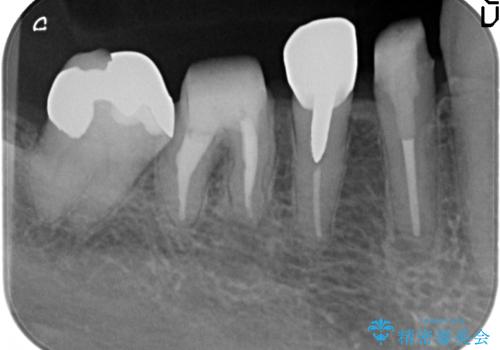

大臼歯 再根管治療

- 銀歯を白くしたいとの希望で来院されました。

せっかく銀歯を白くしても後々根管治療が必要になり、また壊して再治療を行うことを避けたいとの事でしたので、再根管治療から行っていきます。

ただ銀歯を白くするのではなく長期的な予後には歯の内部、根管治療の成功が必要不可欠です。